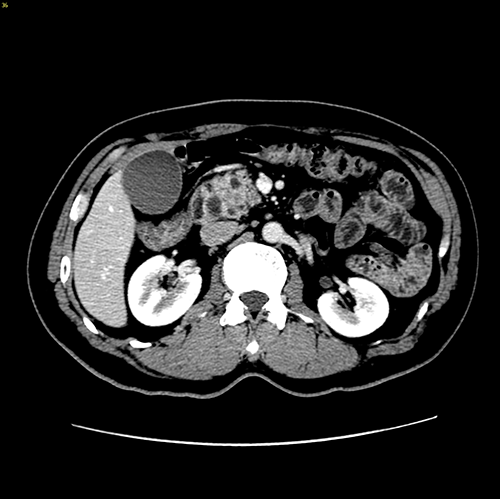

胰头腺癌---胰十二指肠切除